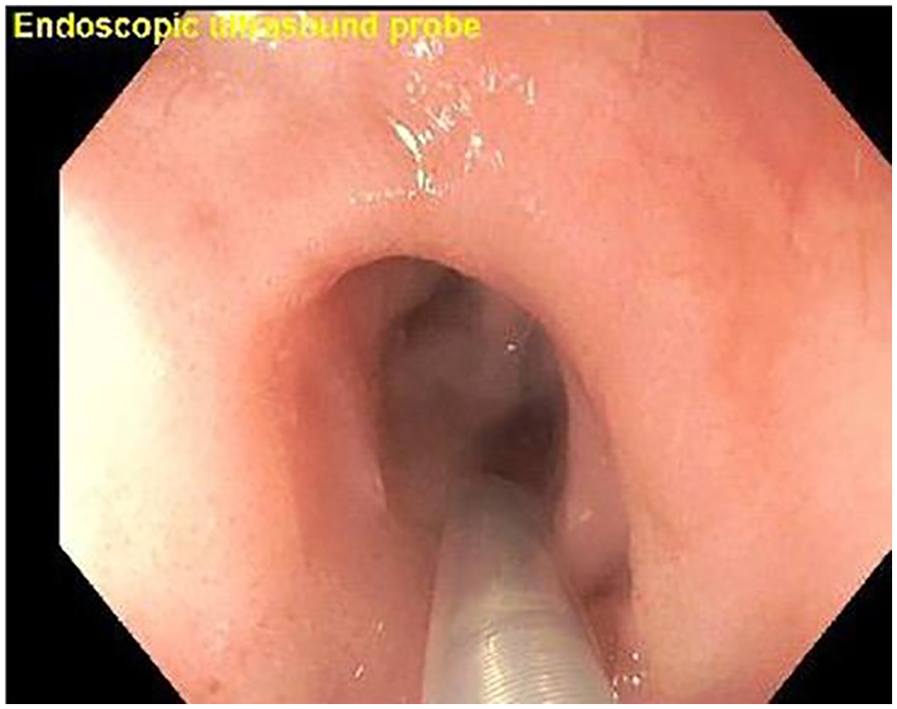

A total of 148 (50.3%) EUS procedures were performed for biliary/hepatic indications. Among them, 100 (67.6%) were performed for suspected choledocholithiasis in whom ultrasound sonography (USG) or Magnetic resonance cholangiopancreatography (MRCP) were inconclusive. Performing an initial EUS, averted a total of 10 (10%) ERCPs (Figure 1).

Figure 1. Endoscopic ultrasound (EUS) demonstrating absence of choledocholithiasis, averting endoscopic retrograde cholangiopancreatography (ERCP).